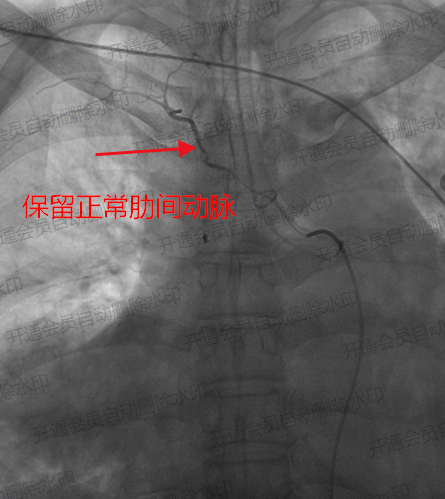

▲保留正常肋间动脉供血

手术过程中,医疗团队规范操作。术中造影清晰显示,患者右侧支气管动脉存在明显扩张迂曲畸形,且有广泛明显的造影剂外渗出血影。随后,医生小心操作,将超选导管送至右侧出血动脉主干,采用1个44mm规格、1个43.7mm规格弹簧圈进行动脉栓塞,再运用适量明胶海绵颗粒进一步栓塞支气管动脉,直至血流停滞。再次造影确认出血影完全消失,左侧肺支气管动脉未见异常。整个手术过程顺利,术后患者恢复良好,症状平稳,最终康复出院。